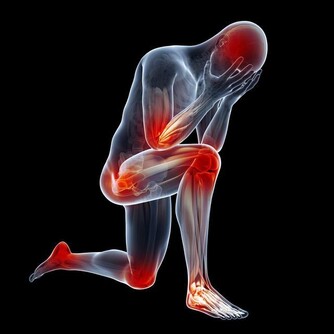

越來越多的證據證明,控制發炎在骨關節炎防治過程中具有舉足輕重的作用。除了藥物消炎之外,合理飲食非常關鍵。美國《預防》雜誌最新載文,刊出多位專家總結出的關節炎患者最佳飲食,幫助他們護好關節。